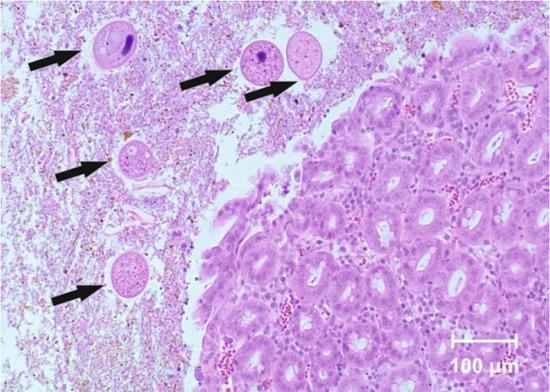

In histological examinations, erosions of caecal and colonic mucosa were found, together with cysts and trophozoites of Balantidium coli. The protozoa were present not only in the intestinal lumen, but also in the intestinal mucosa (Figs 1–3). Parasitological examination with the decantation method confirmed the presence of B. coli cysts in samples of faeces from all examined pigs (Fig. 4). Flotation gave negative results in all samples.

Balantidium coli (arrows) in the intestinal lumen (haematoxylin and eosin, × 100)